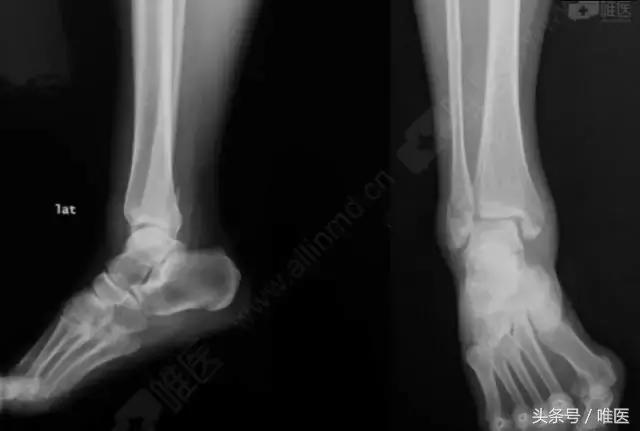

X线:右侧踝关节骨折

L-H分型:旋后外旋型 IV度;

Danis-Webber分型:B型